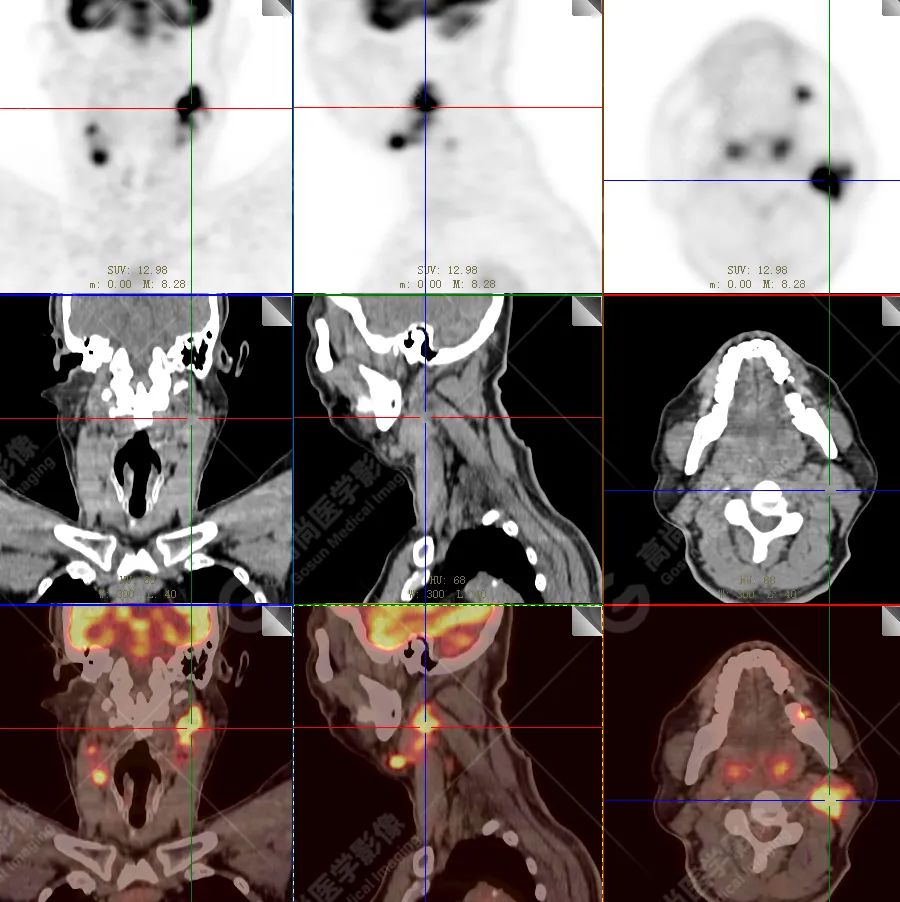

PET/CT 示:

上腭前部见一结节状放射性摄取增高影,大小约 1.6 cm×1.4 cm×1.0 cm,SUV 最大值为 10.5,CT 于上述部位见软组织密度影,边界不清,CT 值约 73 Hu(假牙金属伪影较多致 CT 值偏高)。右侧颈部(Ⅱ、Ⅲ区)及左侧颈部(Ⅰb、Ⅱ、Ⅲ区)见多发结节状及块状放射性摄取增高影,最大约 2.7 cm×2.6 cm×3.1 cm,部分放射性摄取增高,SUV 最大值为 17.7,部分病变内见放射性减低区,CT 于上述部位见增大淋巴结影。

PET/CT 结论:

1. 上腭前部结节状高代谢病灶,多考虑为恶性肿瘤(结合病史,较倾向于黑色素瘤),请结合病理学检查。

2. 右侧颈部(Ⅱ、Ⅲ区)及左侧颈部(Ⅰb、Ⅱ、Ⅲ区)多发淋巴结转移。

病理结果:

恶性黑色素瘤。